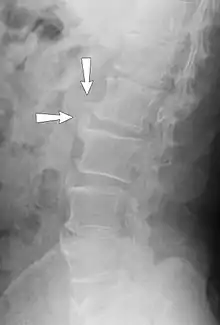

Farmers with long-term exposure to whole body vibration and mechanical shocks have a higher prevalence of back pain (compared to those not exposed to vibration), and the prevalence increases with vibration dose.[11] Long-term exposure affecting the whole body leads to spinal degeneration (spondylosis) and increased risk of low back pain.[12][13]